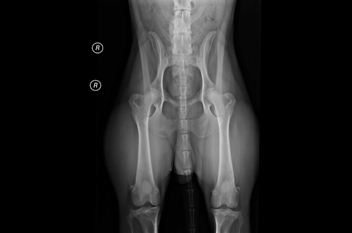

HD/ED/OD-ZUCHTUNTERSUCHUNG

Geprüfter Gutachter der GRSK (Gesellschaft für erbliche Skeletterkrankungen – HD-Zentralen)